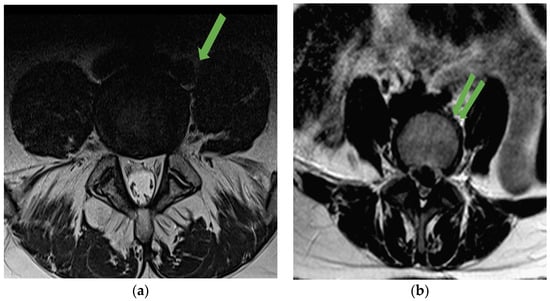

MRI also allows assessment of psoas muscle volume. Bulky muscles, especially at the L4-L5 level, occlude the access window, constituting an obstacle to vessel mobilization. Finally, the characteristics of the dissection plane (Figure 3) of the prediscal space located dorsal to the vasculature should be assessed. On MRI, it is identified as hyperintense tissue on the T2 sequence. The presence of a wide dissection plane indicates that manipulation and mobilization of the vessels will be comfortable. On the contrary, its absence warns us that vessel mobilization will be hazardous.

MRI also allows assessment of the dissection plane between vessels and discovertebral structures. On MRI, this plane appears as bright tissue on the T2 sequence. A wider dissection plane suggests that manipulation and movement of the vessels will be easier. Conversely, if the dissection plane is narrow or absent, it serves as a warning that mobilization of the vessels might be risky or dangerous. MRI is also useful in assessing the degenerative discovertebral process. Malham et al. [21] noted that factors associated with a difficult dissection due to vascular adhesions were the presence of Modic type 2 changes on MRI (OR, 2.1) and smoking status (OR, 2.2). Overall, in the Malham et al. series, 17.5% of patients were classified as having difficult dissections due to vascular adherence. Therefore, the presence of Modic type 2 changes must be considered. The dissection plane can also be altered by the presence of osteophytes. Osteophytic formation is ultimately due to an inflammatory process secondary to the degenerative process of the disc, leading to the formation of a tight adhesion between the vessel (usually the vein) and the osteophyte. In this scenario, the vein is much more difficult to mobilize, and the risk of laceration is greater (Figure 4). In these cases, we recommend that the surgeon dissect cranially and caudally first, leaving the adherent area for the end of the dissection.

Figure 3. Dissection plane can be identified between left iliac vessel and disc (green arrow).